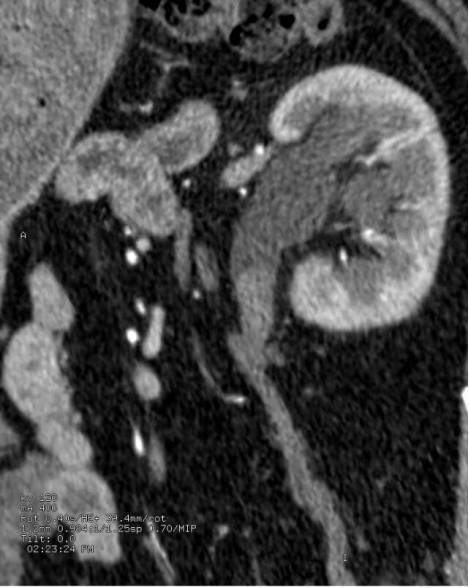

静脉肾盂造影(IVP):

在检查前约12小时,您可能会被要求禁食禁饮水,并且还必须服用泻药来清理肠道。对于检查本身,你需要躺在操作台上进行一系列的X射线检查。然后将造影剂注入手臂的静脉中。你的肾脏可以过滤血液中的造影剂,然后进入泌尿道。在接下来的约30分钟时间内拍摄一系列X射线,以获得造影剂流经肾脏和体外时的照片。在检查过程中,可以对腹部施加压力以使图像更清晰。一旦造影剂到达膀胱,您需要在进行另一次X光检查时排光尿液。